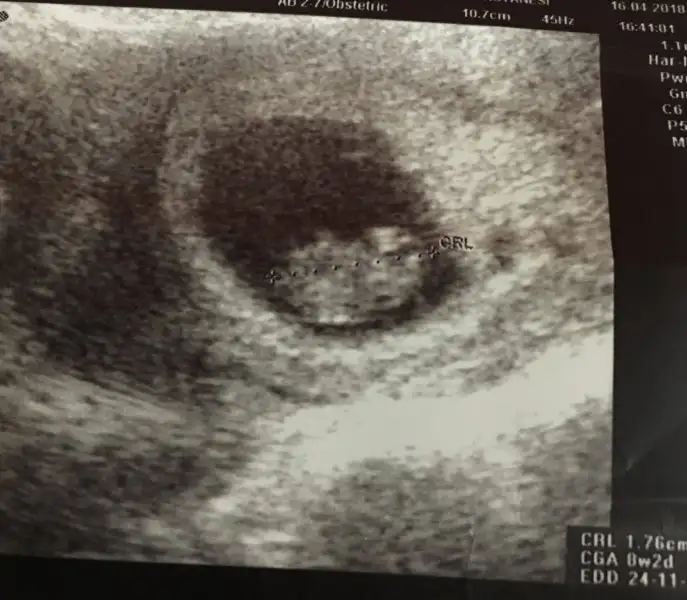

Kızlar 6+1 haftalık görüntü karından. Bana da tahminde bulunur musunuz

Eklentiler

• 57C845F6-3875-4AD1-9908-8A555A704A12.webp

18,3 KB · Görüntüleme: 285

Çok erken ama merak ediyorum sağda gibi değil mi plesentası ilerki haftalarda tekrar danışırım insallah